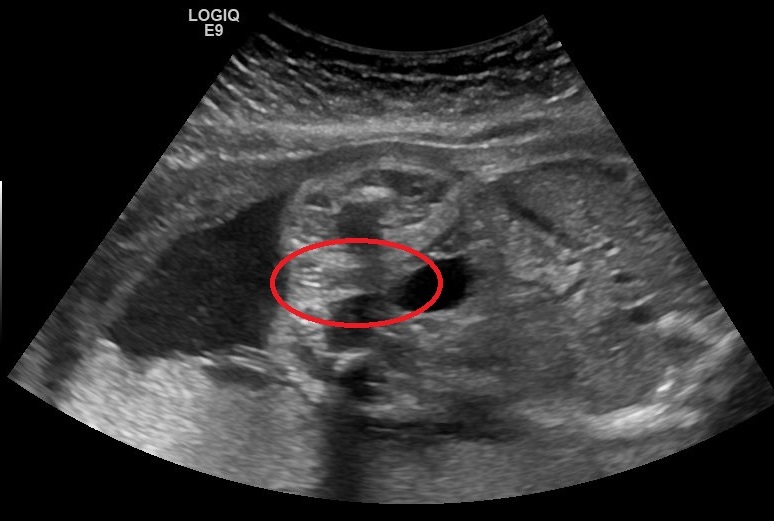

Update i just had my 25 week a 1 day scan please scroll down for latest pics.